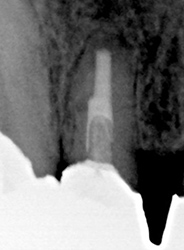

痛くなければこのままで

治療前

治療後

| 主訴 | 腫れておできが出来たが、痛くなければこのままでと言われた |

|---|---|

| 施術内容 | 保存治療と歯根穿孔部の治療 |

| 治療期間 | 3ヵ月 |

| 費用 | 保存治療:110,000円 歯根穿孔非外科的治療:33,000円 相談料:44,000円 |